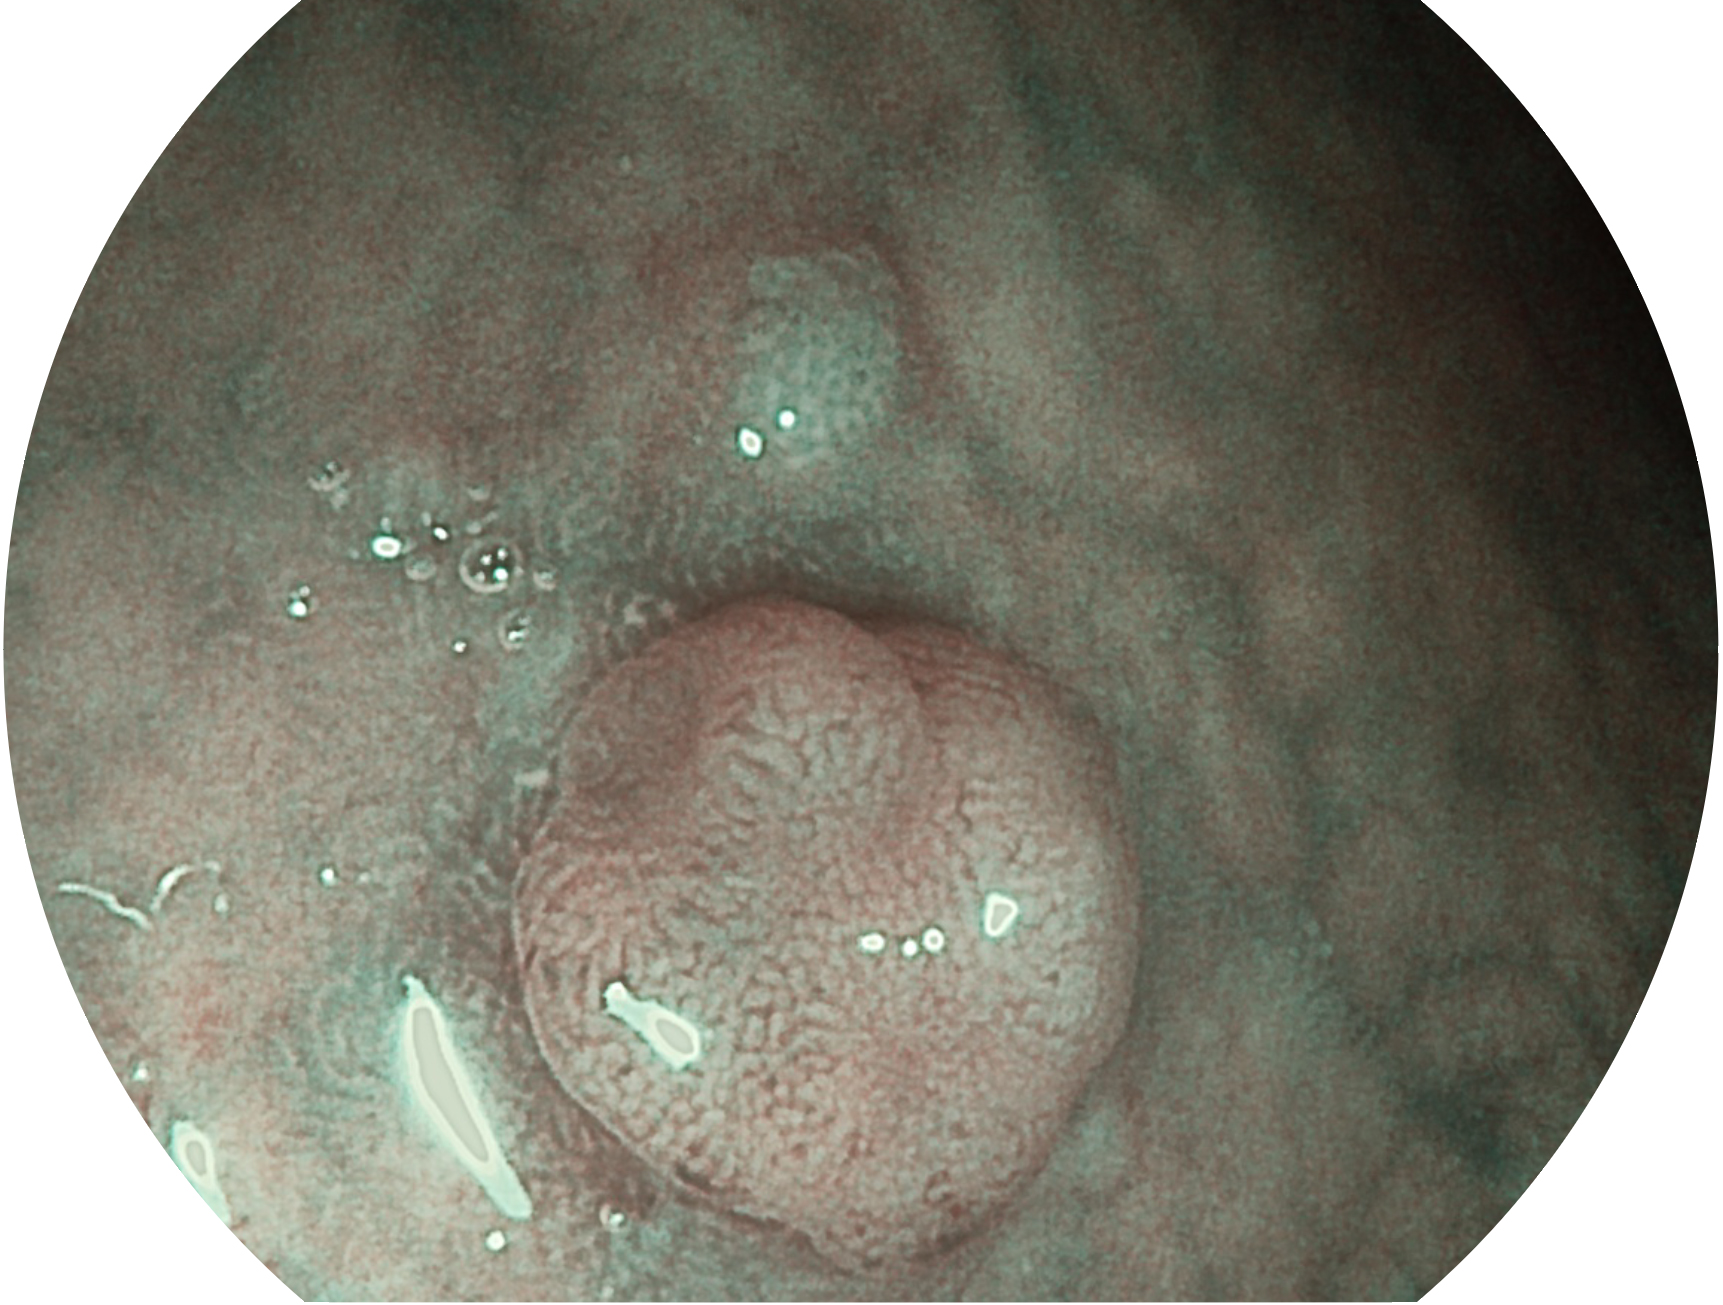

SFI技术是结合特定光谱照明与数字光谱滤波,实现高亮度特殊光成像。染色模式下,不改变粘液、食物残渣、粪液等基本颜色,在保持与白光照明相似的图像色调的同时突显了图像颜色的红白对比度,且在远距离观察的情况下具备与普通白光模式相同的图像亮度,有助于消化道疾病的大范围扫查和早癌筛查。

• 白光图像 SFI图像